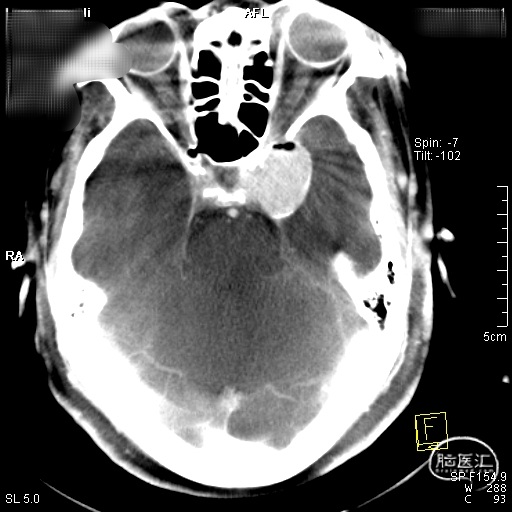

术前CT检查显示,可见左侧侧裂内侧类圆形高密度。

DSA造影显示为左侧颈内动脉海绵窦段巨大动脉瘤。

通过3D工作位测量出左侧海绵窦段动脉瘤尺寸:33mm不规则动脉瘤,载瘤动脉尺寸:近端直径4.55mm,远端直径3.97mm。

造影后发现该患者左侧海绵窦段动脉瘤,动脉瘤不规则,最大径33mm,未破裂,不累及分叉部,动脉路径迂曲。